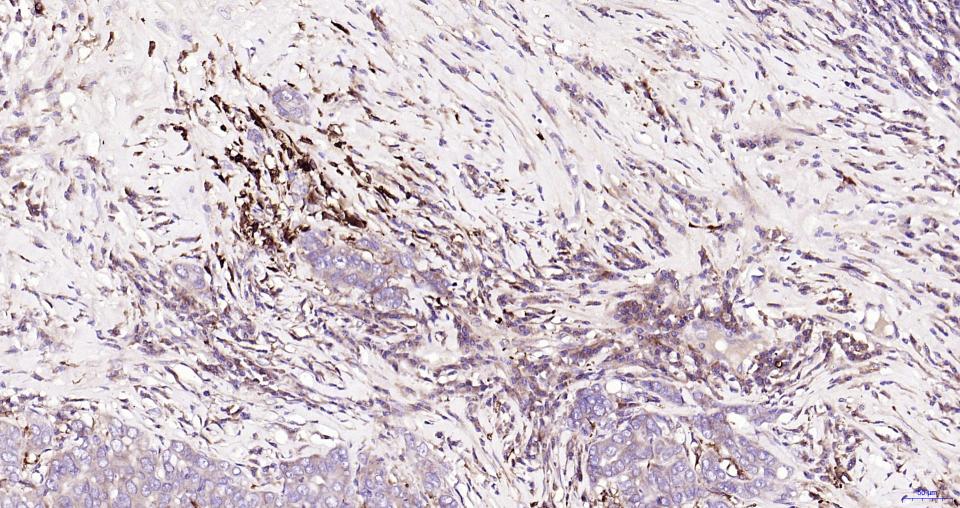

| IHC-P | Human, Mouse, Rat | 1:200-1000 | |